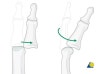

3. 과굴곡 손상 : 전방 탈구(드문 손상)

드문 손상으로 탈구 및 견열 골절이 동반되지 않으면 중앙 신건의 파열을 간과하여 단추 구멍 변형(button hole deformity)을 초래할 수 있습니다.

손상 정도에 따라 중앙 신건이 파열되거나 견열 골절이 동반될 수 있으며, 중위 지골이 전방으로 탈구됩니다.

전방탈구가 있는 경우 종적인 견인으로 정복을 하며, 4주 정도 근위 지간 관절만 완전 시전하여 고정합니다.